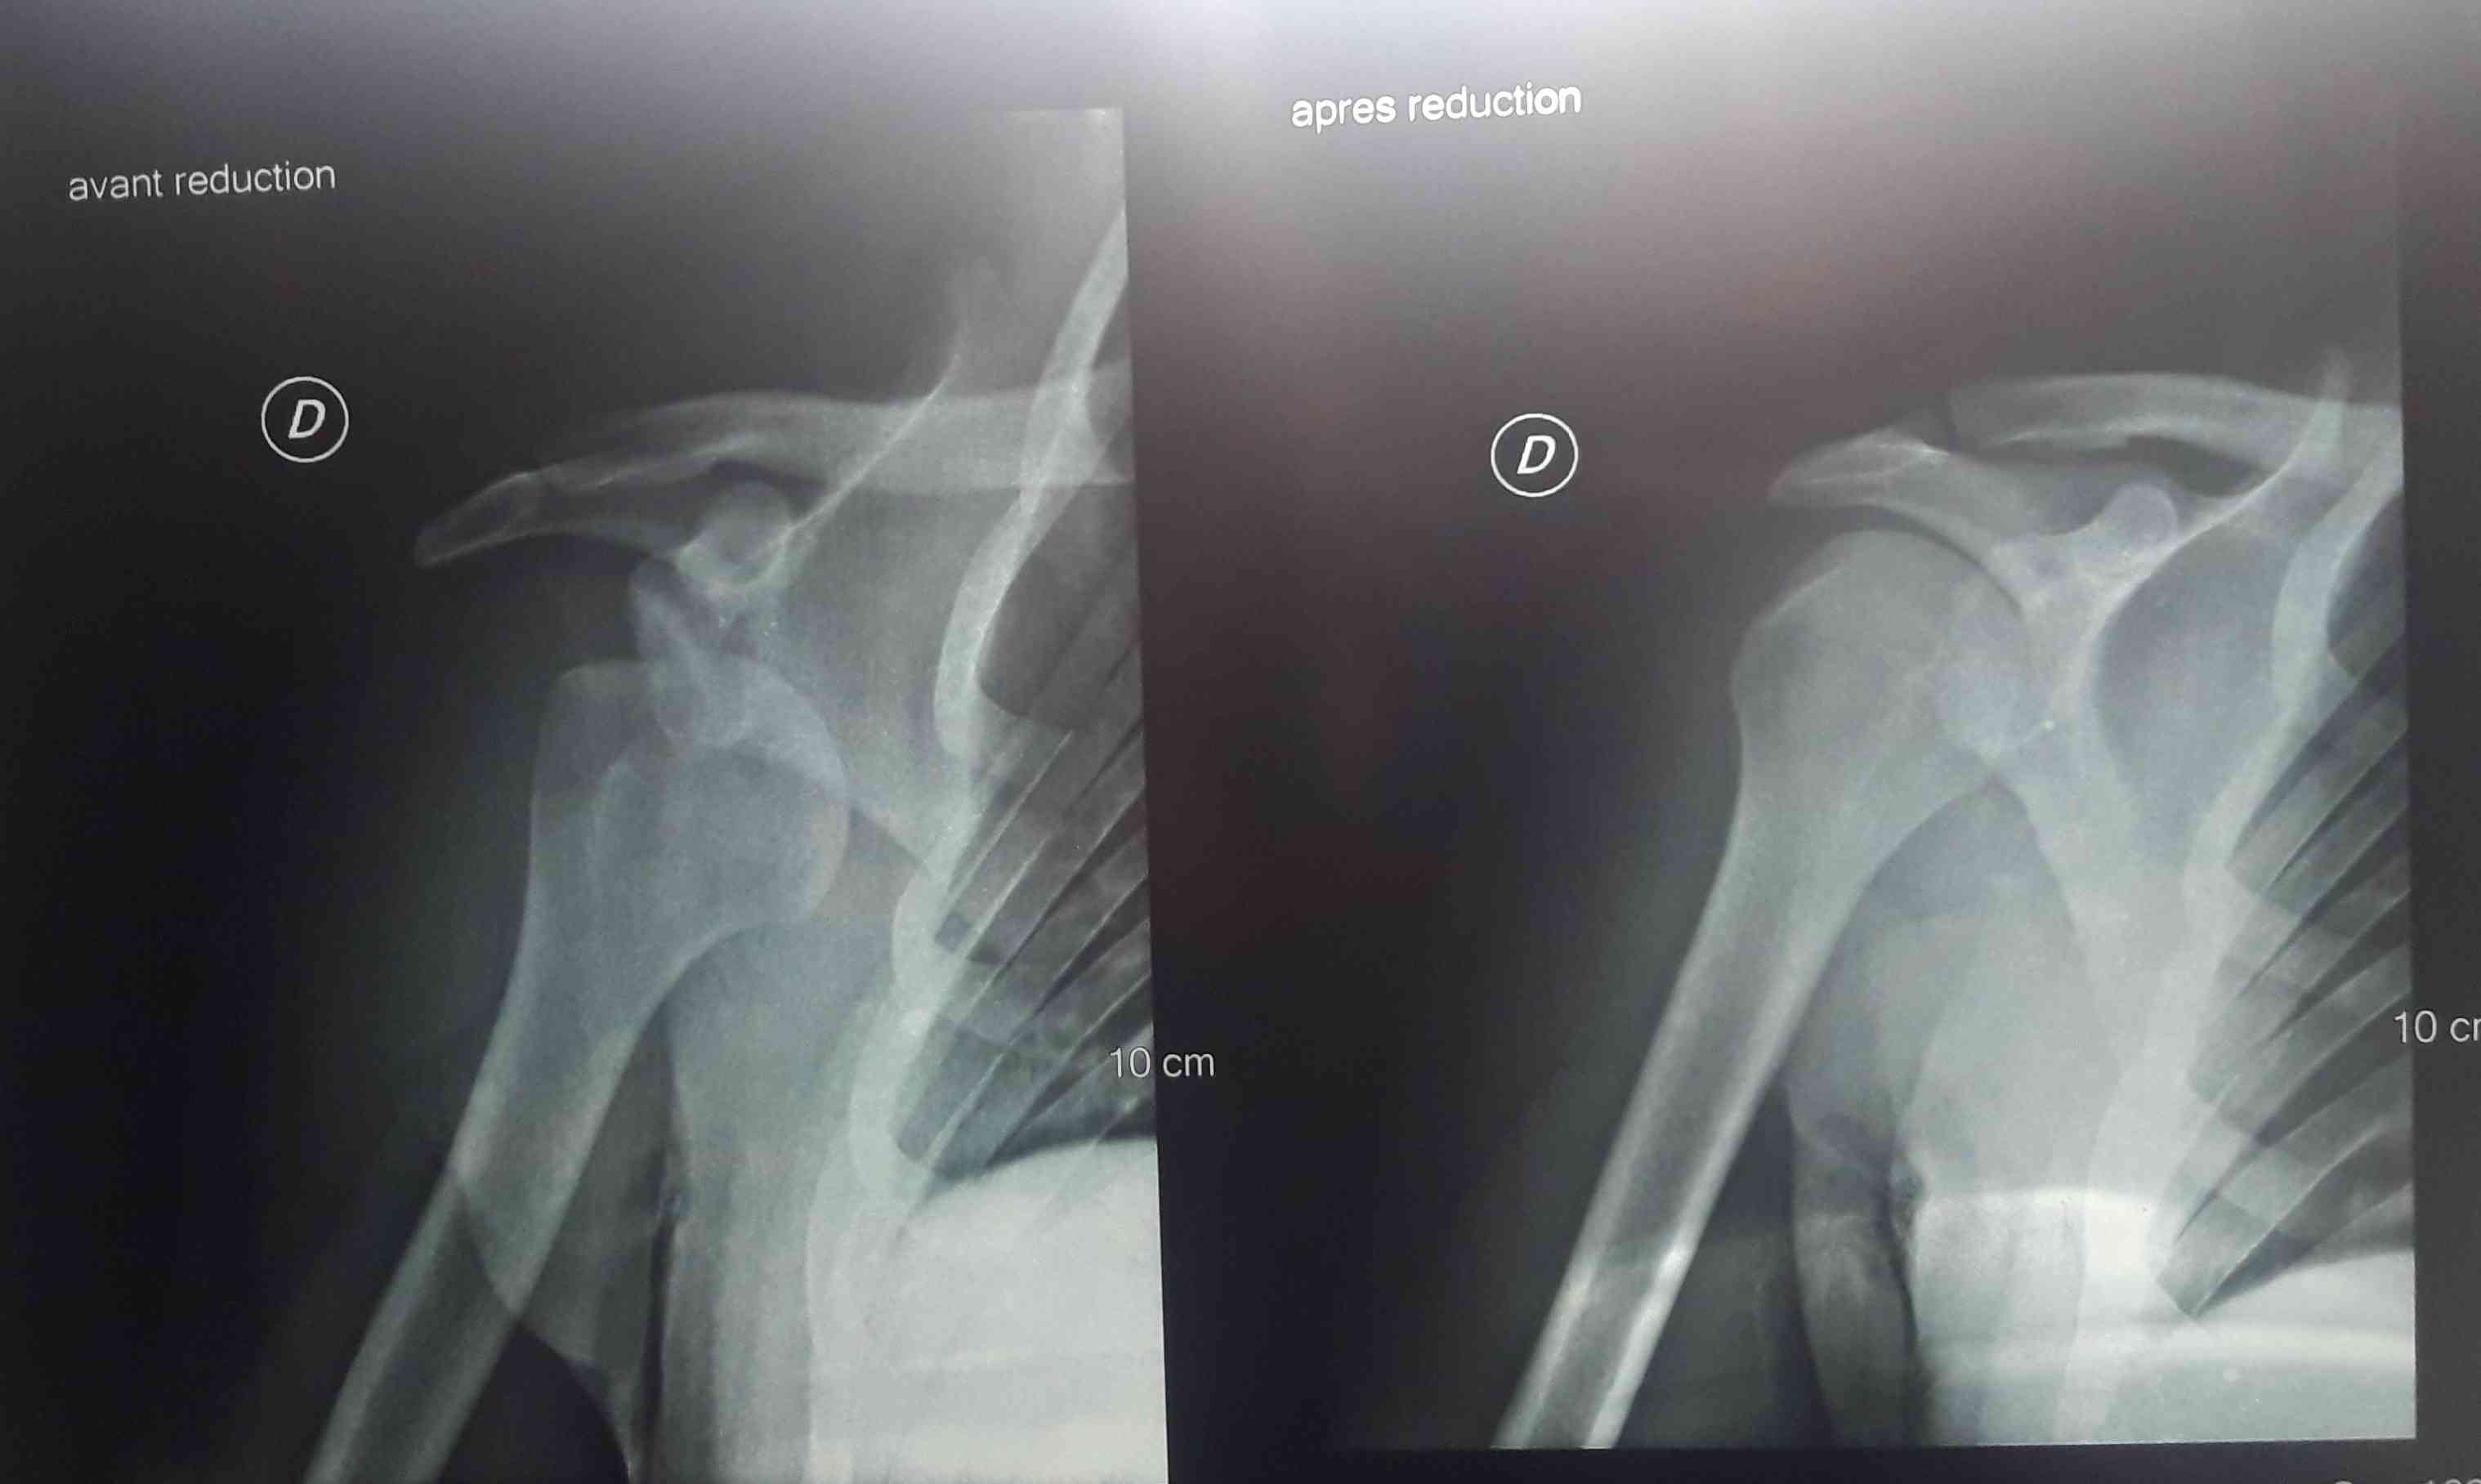

خلع في الكتف اربع مرات

خلع في الكتف له ٥سنوات

خلع في مفاصل الكتف والركبه